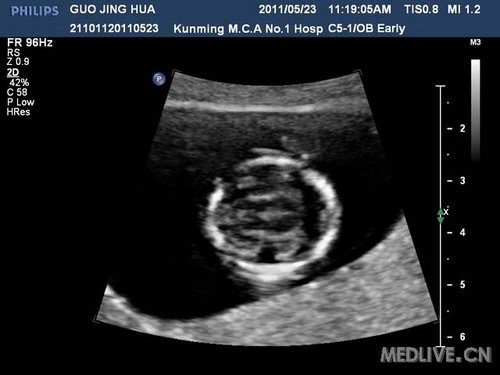

病史摘要:女,25岁,G1P0,从事化工工作,于11周+第一次产检,常规行NT检查时发现:胎儿面部扁平,脑中线显示不清,胎心快,根据FM提供软件计算13-三体风险值为39,建议孕妇绒毛活检,未同意,嘱两周后复查。

复查时发现:胎儿鼻子位于双眼之间,呈喙鼻状,脑内结构紊乱:正常结构(侧脑室,丘脑)不能很好分辨,不能显示两个侧脑室,两侧丘脑,仅可见一个较大的原始脑室。

(1)脑内结构紊乱:正常结构如侧脑室,丘脑,不能很好分辨,不能显示两个侧脑室,两侧丘脑,仅可见一个较大的原始脑室,中央见单一丘脑回声结构,呈融合状。脑中线结构消失,如脑中线回声消失,透明隔腔及第三脑室消失。胼胝体消失,脑组织变薄。

(3)早孕期变现:早孕期不能显示大脑镰,胎头呈“气球样”。